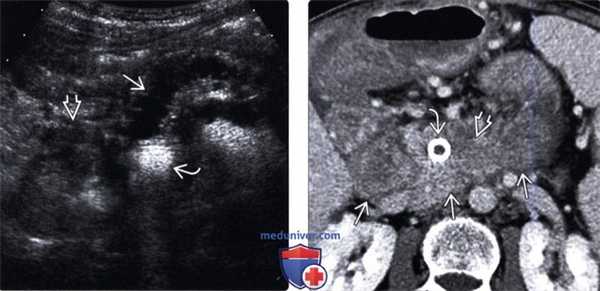

(Левый) На поперечном срезе брюшной полости визуализируется извитой расширенный панкреатический проток. Головка поджелудочной железы скрыта газами стента общего желчного протока. Обратите внимание на опухолевидное увеличение двенадцатиперстной кишки.

(Правый) При КТ с контрастным усилением на аксиальной томограмме значительно лучше визуализируется объемное образование сниженной плотности с нечеткими контурами, инфильтрирующее перипанкреатическую жировую клетчатку и прорастающее двенадцатиперстную кишку. Визуализируется стент общего желчного протока.